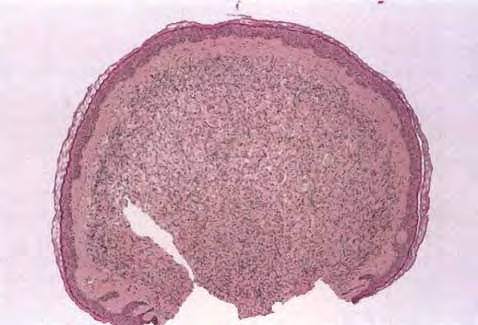

Neurofibroma = الليفوم العصبي